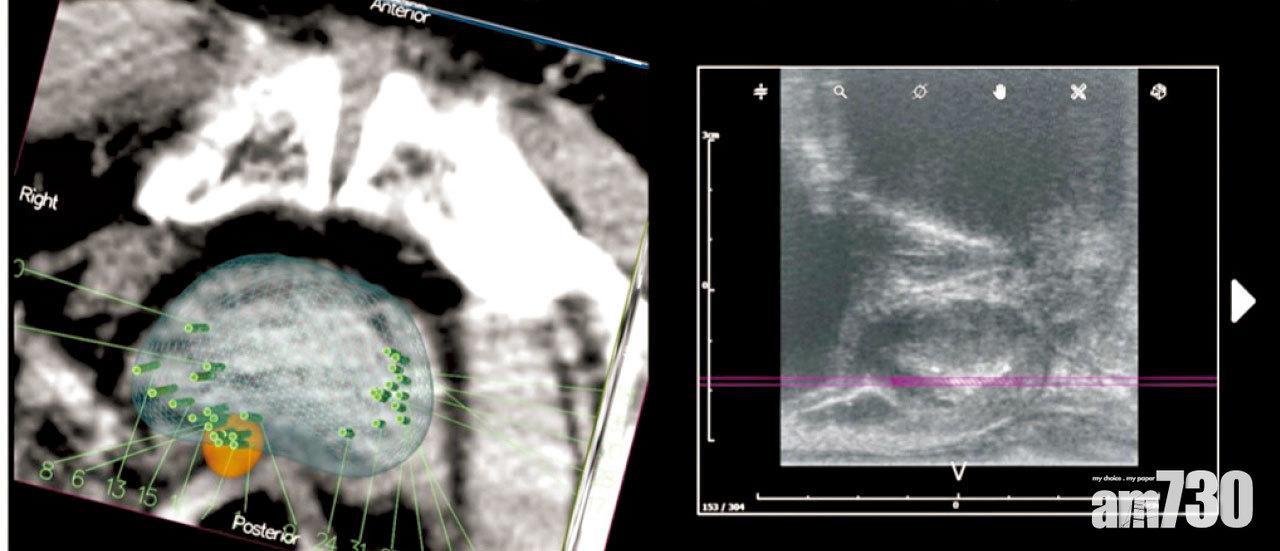

最近醫學界更引入Prostate Surface Membrane Antigen(PSMA)正電子掃描,對偵測前列腺癌細胞的敏感度高達85%至97%,配合即時的聲音影像,能增加可疑組織穿刺的成功率。同時可以清楚全身的癌細胞的轉移情況,大大提高診斷準確度,同時為醫生提供更多資料,更準確地選擇最適合病人的治療方案。

利用最新的正電子掃描,在可疑的前列腺癌組織附近定位(綠色點),找出更準確的抽針位置以作活檢。右圖為同一前列腺位置的超聲波圖像。